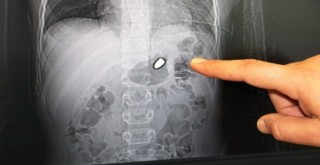

Akıl almaz olay! 10 yaşındaki çocuğun göğsünden çıkartıldı